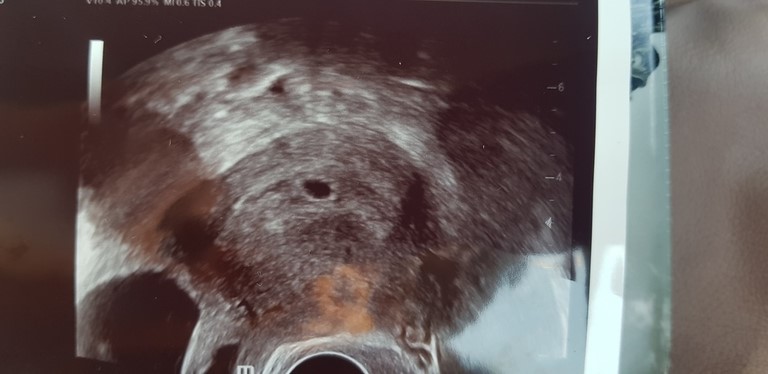

Я БЕРЕМЕННА !Я была на УЗИ, увидели моего малыша) Располагается очень хорошо, прям по центру) Теперь нас ждут с мужем через две недели слушать сердечко) И я скажу так, мы его услышим, потому что наш малыш молодец, и мы его уже безмерно любим!)

Я такая радостная сегодня, увидеть свою бусинку - это фантастика) Глаза на мокром месте все время. Делюсь нашей первой фоткой с вами! Спасибо всем, кто поддерживал меня и не давал впадать в паническую истерику. Вы лучшие! Всеми-всеми делюсь снова лучами добра, и в ваш дом обязательно придет такая радость! Обязательно!